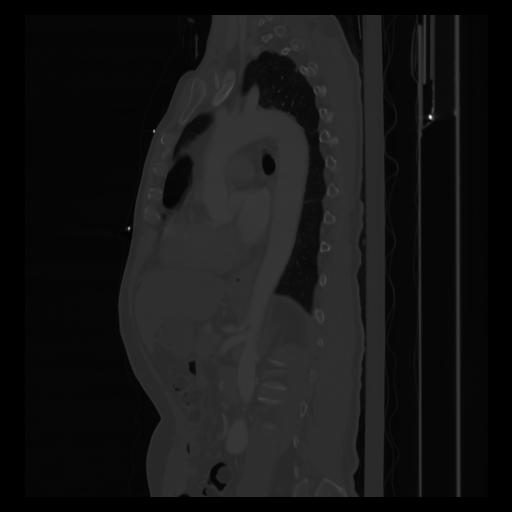

30 CUERPO,CE,Sagittal,3.000,CUERPO,Sagittal,